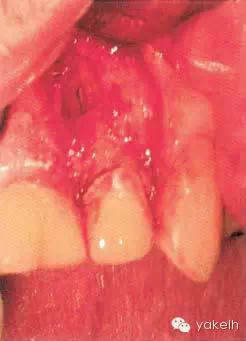

¤¤在征得患者同意后,最終選擇根管外科手術(shù)修復(fù)穿孔。局麻下翻開三角形全厚黏骨膜瓣,充分暴露骨和根面;使用刮匙去除穿孔上覆蓋的肉芽組織,暴露穿孔和樁(圖5.4.2a);使用外科專用渦輪手機(jī)配以金剛砂小球鉆,去除樁的尖端;使用超聲銼去除根管末端的牙膠,并進(jìn)行根管預(yù)備(圖5.4.2b);預(yù)備后的根管與穿孔部位使用IRM嚴(yán)密封閉(圖5.4.2c);瓣復(fù)位、縫合固定,拍攝術(shù)后X線片(圖5.4.3a);3天后拆線。

¤¤術(shù)后1年復(fù)查,竇道未復(fù)發(fā),軟組織無壓痛,X線片顯示根周骨組織愈合良好(圖5.4.3b)。

圖5.4.2(c)根管末端和穿孔部位使用IRM封閉。